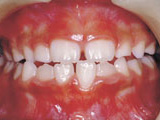

症例2:乱ぐい歯「歯並びが乱れている」

治療前 治療後